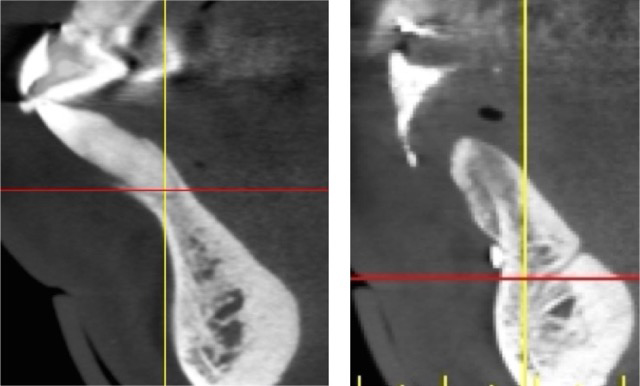

Fig 4. (Left) Grade I socket with an intact buccal plate demonstrating less than 25% bone loss; (Center) Grade II socket showing fissure, dehiscence, and approximately 50% buccal plate loss; (Right) Grade III socket with more than 50% buccal plate loss.

Figure 4